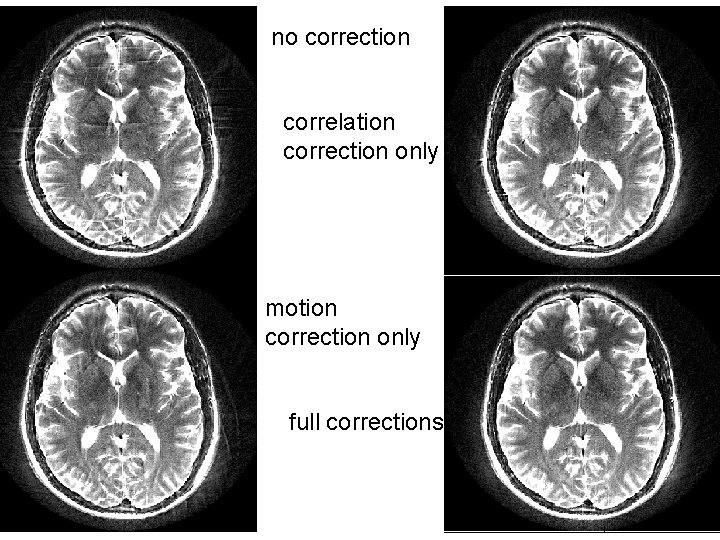

no correction correlation correction only motion correction only full corrections